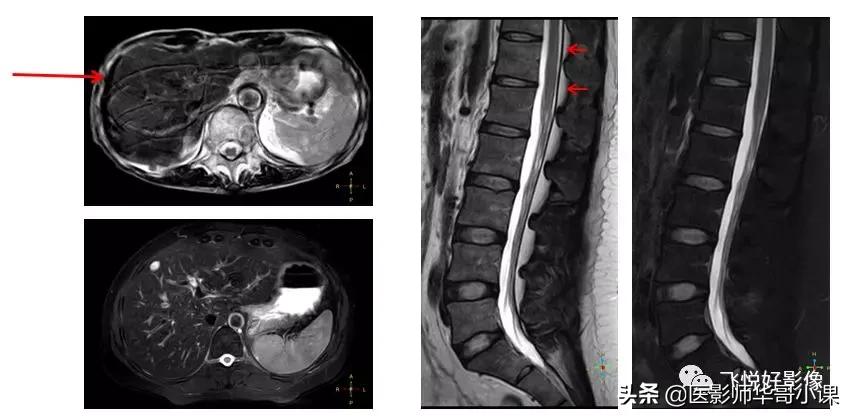

通过脂肪抑制,还可以减少运动伪影、化学位移伪影。左边这一组图是我们临床常用的腹部T2加权像,上面一幅我们可以明显看到,有许多条形伪影,它是由于腹壁脂肪高信号随呼吸运动产生的伪影。施加脂肪抑制以后,伪影明显减轻。右边这组图是腰椎矢状位T2及T2压脂图像。大家仔细观察一下,可以发现在不压脂T2图像中脑脊液与硬膜囊后方脂肪组织之间出现了一条信号丢失带,呈一个明显的勾边线影,这是水-脂的化学位移伪影;采用压脂技术后,勾边带消失。所以,有时候脂肪抑制可以减少一些脂肪相关伪影。